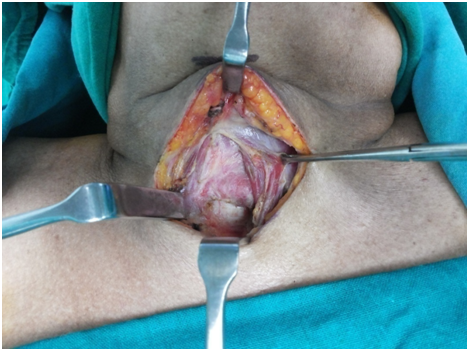

After identifying the landmarks (Figure 5) the neck was explored by a transverse 6 cm incision just on the upper border of the felt pulsation of the vessel. Skin, fat and platysmal incised and upper flap was raised to expose the investing layer of cervical fascia. The lower flap was deliberately not raised to prevent exposing the vessel. This fascia was split in the midline to expose the strap muscles and the isthmus of thyroid gland (Figure 6). The isthmus was split in midline and the edges transfixed to the ipsilateral Sternothyroid muscles (Figure 7). Both sides Sternohyoid muscles were cut at their upper ends, rotated and sutured to the other side (Figures 8&9) sternothyroids making a muscular bed over the horizontally running brachiocephalic trunk just underneath. An inverted “U” flap on the exposed 2nd to 4th tracheal rings was incised and was sutured to the unraised subcutaneous layer of the lower skin flap overlying the vessel hence forming another barrier and a bed for the tracheostomy tube so that it does not rub against it any of the time (Figure 10). Skin incision was closed leaving the opening for the trachoestoma. Portex cuffed tracheostomy tube with suction aid inserted after withdrawing the endotracheal tube.

Figure 6 Thyroid Gland and Trachea Exposed

Figure 7 Thyroid split